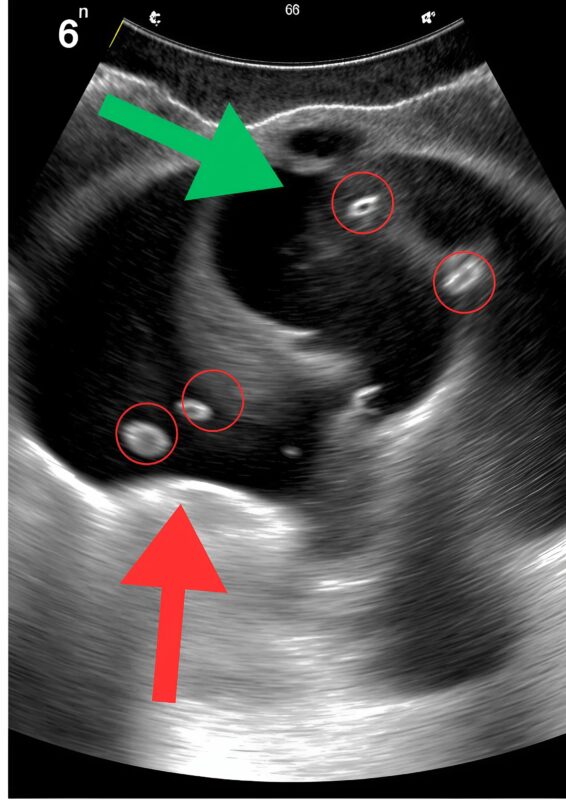

A doctor arrived quickly, calm but focused. He pressed gently on my abdomen, and I cried out despite trying to stay composed. After blood tests and an urgent ultrasound, he returned with a look that was serious—but not panicked.

Gallstones.

Tiny, hardened stones had formed inside my gallbladder, blocking the bile duct and causing severe inflammation. One stone had become lodged in exactly the wrong place, triggering the unbearable pain and constant vomiting. If left untreated, it could lead to infection, rupture, or even sepsis. The pain wasn’t random—it was my body screaming for help. ⚠️🩺